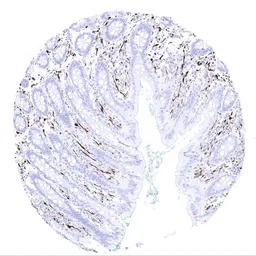

IHC-P analysis of human appendix mucosa tissue section using GTX04404 S100 antibody [MSVA-490R] HistoMAX.

IHC-P analysis of human brain cerebrum grey tissue section using GTX04404 S100 antibody [MSVA-490R] HistoMAX.